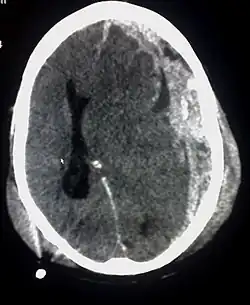

Als Hirnblutung oder intrakranielle Blutung (Haemorrhagia cerebri) werden Blutungen im Inneren des Hirnschädels, also im Bereich des Gehirns (intrazerebrale Blutung) oder der Hirnhäute (extrazerebrale Blutung) bezeichnet. Erstere entsteht meist plötzlich, insbesondere bei Menschen mit Bluthochdruck, und äußert sich als Schlaganfall. Im weitesten Sinne zählen zu Hirnblutungen auch die Subarachnoidalblutung, Epiduralblutung und Subduralblutung, die beim Schädel-Hirn-Trauma oder Gefäßanomalien auftreten. Hirnblutungen können lebensbedrohlich sein. Viele Patienten mit einer Hirnblutung können neurochirurgisch erfolgreich behandelt werden. Die Inzidenz der Hirnblutung in Deutschland liegt zwischen 10 und 12 je 100.000 Einwohnern.[1]

Intrakranielle, intrazerebrale Blutungen

Die intrazerebrale Blutung liegt im Gehirn und resultiert in einer Beeinträchtigung der Hirnfunktion, für die das betroffene Hirngewebe benötigt wird. Durch Größe und Lokalisation der Blutung wird deren raumforderndes Verhalten bestimmt. Gefürchtet ist die mit einer Mortalität von 50 bis 60 % im ersten Jahr nach der Blutung einhergehende[4] Hirnmassenblutung, die große Teile des Gehirns zerstört und zu einer Einklemmung führen kann.